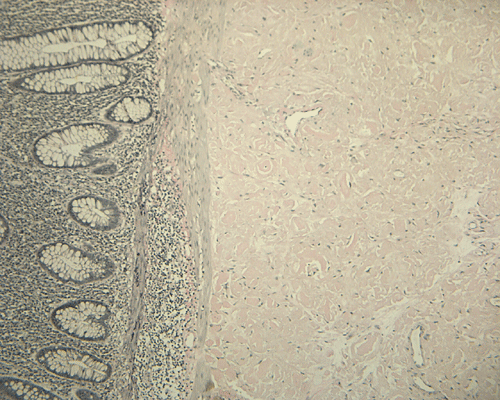

On low magnification, the mucosa appear intact and unremarkable. However, the submosa and muscular layer is replaced by a pale eosinophilic, hypocellular, amorphous material (Panel A). These material separate the smooth muscle bundles (Panel B and C). On Masson's trichrome, these material appears blue (Panel D). They are negative for elastic stain (Panel E). These material are stained orange by Congo Red stain (Panel F and G) which gives an apple green birefrigence on polarized light (Panel H). Electron microscopy was performed and revealed non-branhing straight fibrils ranging from 6.6 to 8.3 nm in diameter consistent with amyloid.

Immunohistochemistry was performed and showed strong reactivity for lambda light chain. Numerous plasma cells within the mucosa overlying the amyloid deposition are also postive for lambda light chains. The results suggest a monoclonal lambda light chain plasma cell dyscrasia but it could not be further classified in the excised specimen.